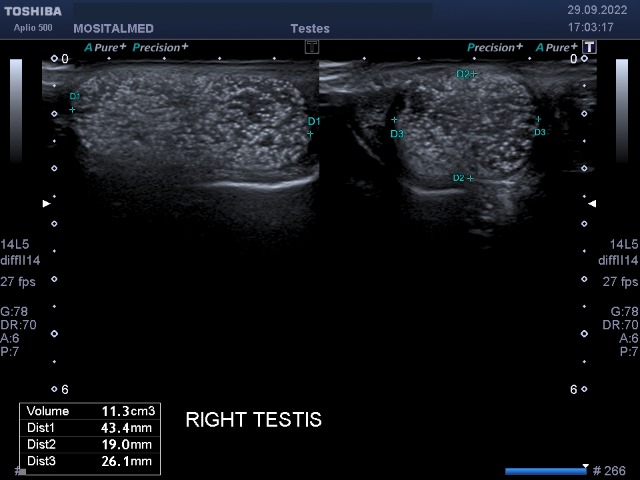

Редкий случай, коллеги.

Сплошные микролиты в ткани обоих яичек.

Я впервые встретил такой тотальный микролитиаз.